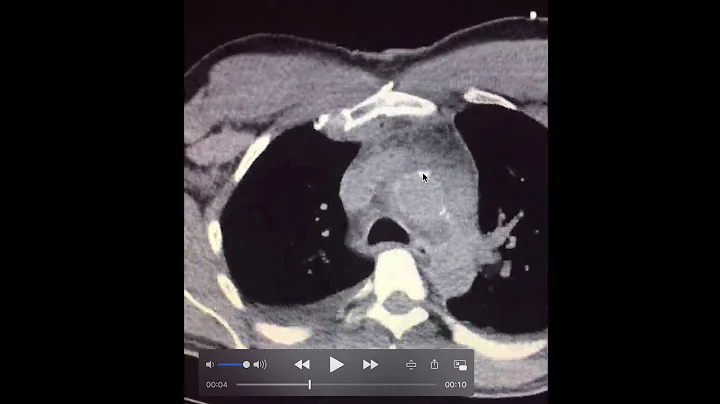

"3 Things I Wish I Knew Before My Ct Heart Scan"

A CT heart scan that yields a coronary calcium score is a wonderfully useful and empowering test to have. It yields a reliable ...